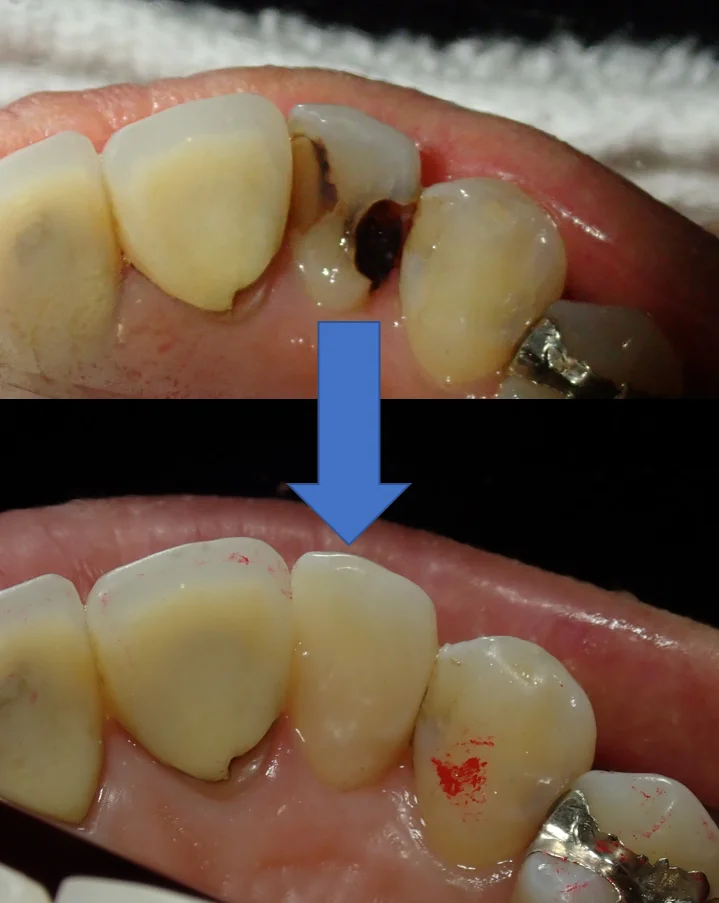

最後に術前術後の写真を載せて終了したいと思います。

裏側から見るとこんな状態になってしまっていました。

前後の歯の間から虫歯が入り込み、歯の中央で虫歯が繋がっている状態となっています。

裏側がこんな感じです。

本来なら全周削って被せる「クラウン」形態になるような状況でしたが、無事に歯質を多く温存できたかと思います。